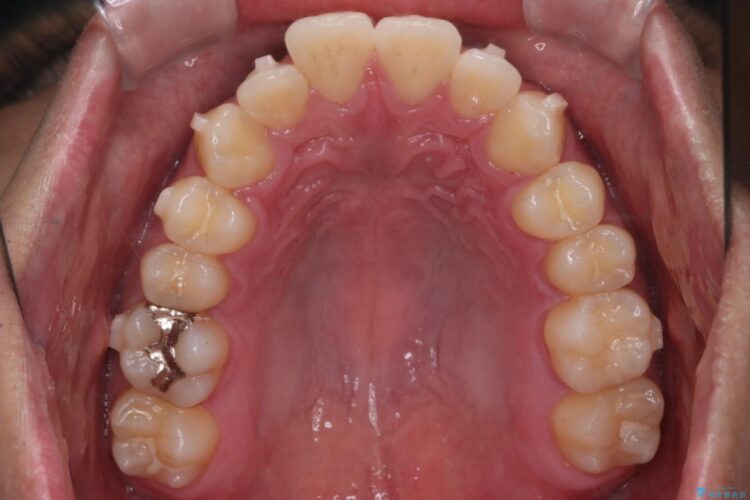

上の前歯が出ているのが気になるとご来院された患者様です。

IPR(歯と歯の間を削る処置)を行うことで、前歯の位置とがたつき整える治療計画を立てました。

患者様はシミュレーション通りに歯が動くのかと心配されていました。

可能な限り計画通りに歯を動かすために、マウスピース1枚あたりの使用時間を長めに使っていただきました。

そのため、多少治療期間が延びましたが、リファイメント(マウスピースの再発注)なしで終了することができました。